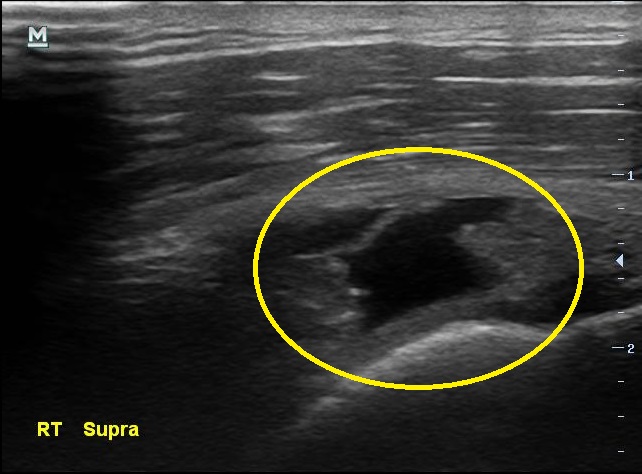

3개월만에 통증이 더 심해졌다고 찾아온 남자분, 검사 결과는 3개월전보다 더 악화 되었습니다.

초음파 검사 결과 3개월전에 비해 극상근 힘줄의 파열 정도가 더 심해져있습니다.

나 : 초음파에서 이정도 소견이면..... MRI 촬영하고 필요하면 수술도 고려해보아야 할 정도네요